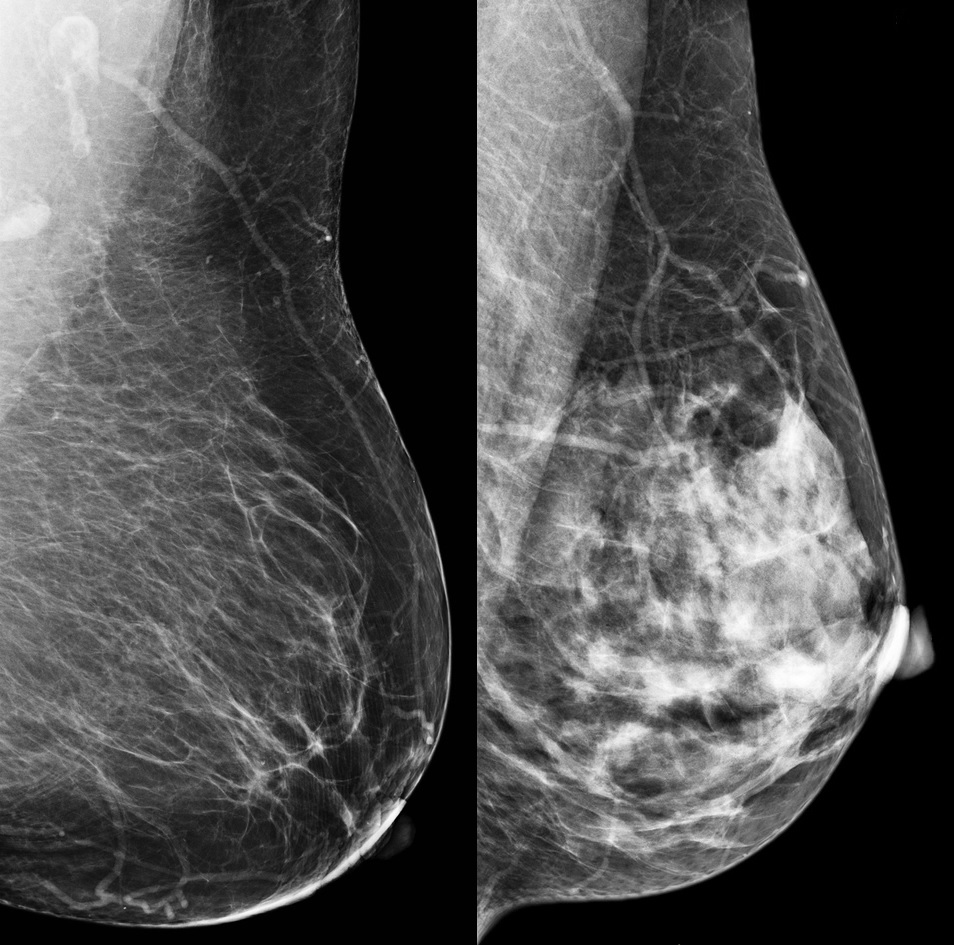

If you are someone who has denser breasts, which is more likely for younger women, women who are pregnant and/or lactating, and women with lower body fat then it is important to have conversations with your doctor about your risks and screening tests needed for early detection. Some recommendations may include a mammogram, ultrasound, or even an MRI. I am sharing a photo of a mammogram that compares a breast which has mostly fatty tissue (left photo) with a breast which has dense tissue (right photo).

Source: Centers for Disease Control and Prevention Website